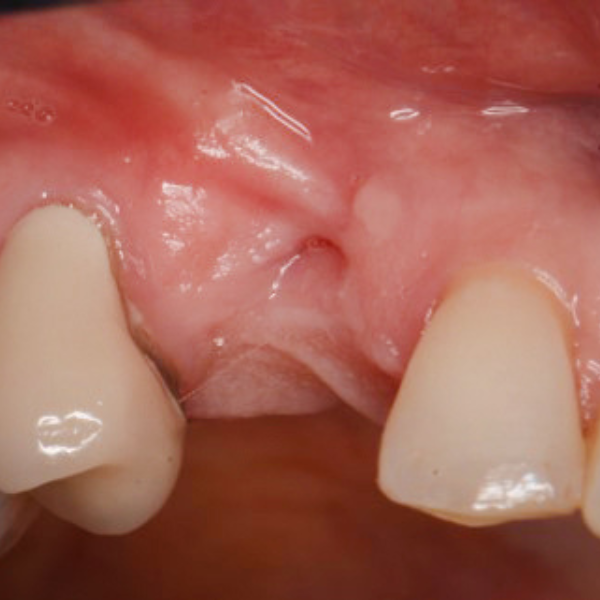

UL5 Extraction and Implant Placement

Patient suffered from a root fracture. Needed removal and to restore hard and soft tissue.